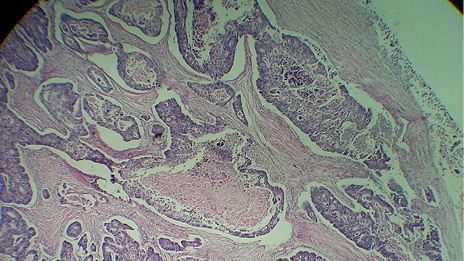

Figura 4. La pieza macroscópica corresponde a un segmento de intestino grueso el cual presenta solución de la continuidad de su pared donde se observa una gran perforación con bordes irregulares y engrosamiento de la misma al corte la mucosa sobre la lesión es de aspecto nodular exofítico que ocupa parte de la luz intestinal y afecta concéntricamente. Fuente: Laboratorio de Anatomopatología del HGZ No. 35.

El departamento de Anatomopatología reporto la pieza como un adenocarcinoma de tipo intestinal moderadamente diferenciado con extensión hasta los tejidos blandos pericolónicos e invasión vascular (Figura 5 y 6).

Figura 5. Los cortes histológicos teñidos con tinción de rutina H&E muestran una proliferación difusa de elementos glandulares atípicos con anaplasia celular marcada y presencia de necrosis sucia intraluminal. Fuente: Laboratorio de Anatomopatología del HGZ No. 35.